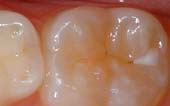

Your pediatric dentist may also recommend protective sealants or home fluoride treatments for your child. Sealants can be applied to your child’s molars to prevent decay on hard to clean surfaces.

A sealant is a protective coating that is applied to the chewing surfaces (grooves) of the back teeth (premolars and molars), where four out of five cavities in children are found. This sealant acts as a barrier to food, plaque and acid, thus protecting the decay-prone areas of the teeth.